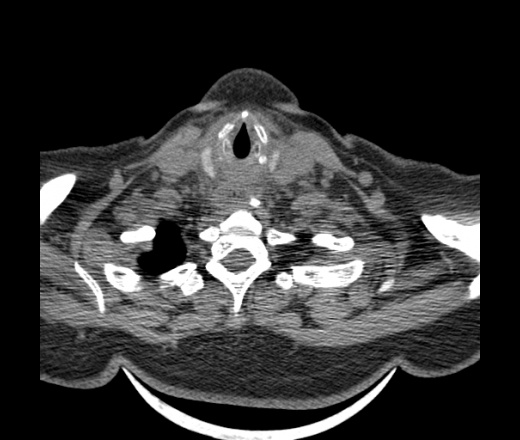

Женщина поступила в х/о спустя 4 дня после того как при употреблении карася подавилась костью.

Наличие газа в средостении на протяжении тел С2-С6 (медиастинальна эмфизема); рыбная кость на уровне тела С6.

При всем уважении, но говорить о медиастинальной эмфиземе, оценивая мягкие ткани шеи, как-то слишком резко. На мой взгляд, это ретрофарингеальное пространство.

Эвакуировали почти 100мл гноя. Но кость не смогли найти. Думаю что она даст дальнейшее ослоднение. Эндоскопически за черпалонадгортаной звязкой не смогли зайти в пищевод, все мягкие ткани отечные, просвет пищевода сдавлен. По всей видимости параэзофагеальная клетчака тоже задействована. Эмпиема, если ее можно так назвать, незнаю как правильно дошла до уровня яремной вырезки. Чем закончиться напишу. Ждем медиастинита.

Согласен с Вами; конечно, наличие газа в клетчатке ретрофарингеального пространства (затмение с опечаткой..). К сожалению, процесс "продвигается" к медиастиниту. Но почему никто, не отмечает наличие рыб. кости; или это для Всех очевидно?

Кость то мы сразу выявили, размеры где то 17*2мм, но ее так и не получается найти в этой каше